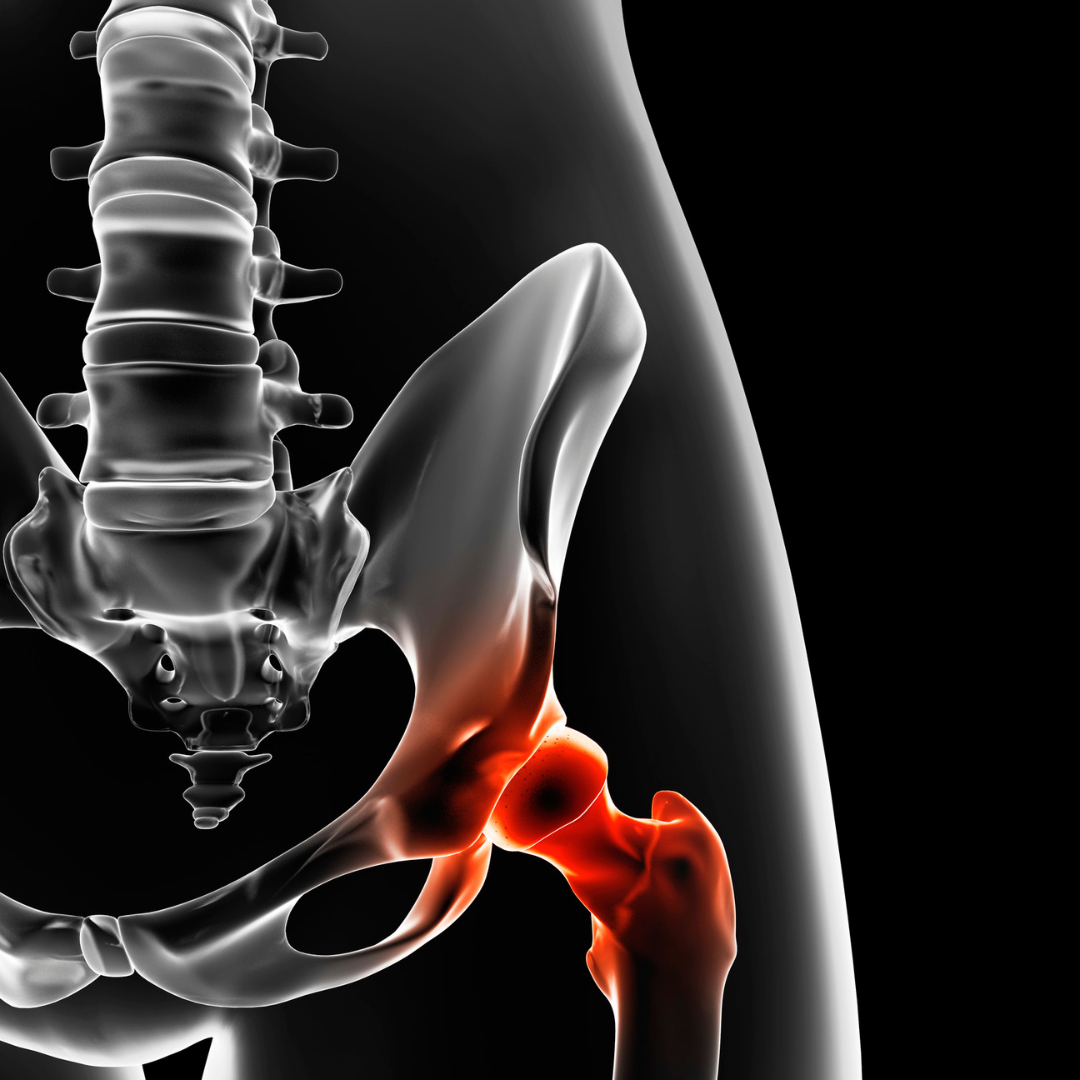

VALORACIÓN FUNCIONAL DE LA CADERA

La cadera es una articulación tipo enartrosis; (presenta un amplio rango de movilidad) en la que pueden aparecer patologías entre las que se encuentran la artrosis, la trocanteritis, la bursitis, etc. Podemos enontrar también por su forma anatómica lo que denominameos choques femoroacetabulares, displasias, etc. Los desequilibrios musculares que generan la pérdida progresiva de fuerza en los músculos de esta articulación, así como la falta de flexibilidad, el envejecimiento; (que a su vez cursa con degeneración ósea y del cartílado), el sobreentrenamiento o exceso de esfuerzo, son todos ellos factores predisponenetes a aumentar el riesgo de lesiones.

En este taller aprenderemos a hacer una valoración funcional para detectar las principales patologías que afectan mayoritariamente a esta articulación.

Montse Herrero (fisioterapeuta y PNIE) para Master-D Barcelona

17-JUNIO-2024

EJERCICIO TERAPÉUTICPO PELVIS/CADERA

Son frecuentes las patologías que cursan con una mala movilidad de la pelvis y de la cadera, como lumbalgias, impingement, pubalgia, incluso síntomas patológicos en la articulación de la rodilla.

En este taller repasaremos la tendencia actual en cuanto al ejercicio terapéutico aplicado a este complejo articular.

Montse Herrero (fisioterapeuta y PNIE) para Master-D Barcelona

28-OCTUBRE-2024

TRATAMIENTO DE LA TROCANTERITIS MEDIANTE TERAPIA MANUAL

La trocanteritis es una inflamación dolorosa en la región del trocánter mayor de la cadera. El masaje terapéutico utiliza técnicas especializadas para eliminar bandas tensas musculares, puntos gatillo y reducir la inflamación en la zona trocantérea.

En este taller expondremos algunas técnicas que pueden ser efectivas para el tratamiento de esta patología.

Montse Herrero (fisioterapeuta y PNIE) para Master-D Barcelona